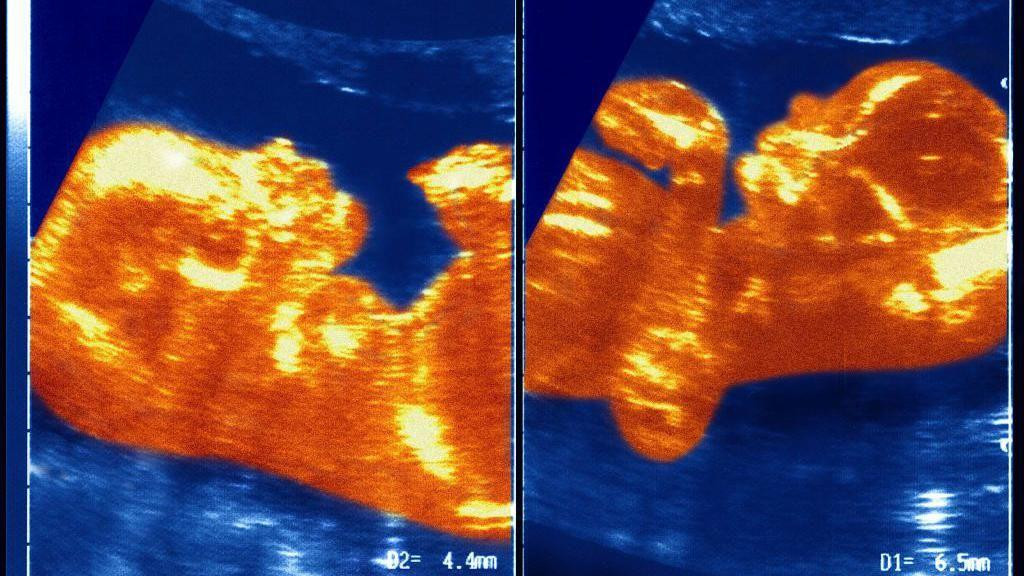

Fotografije Ane Paule i njenog brata blizanca

Smatra se da je prvi zabeležen ovakav slučaj, a lekari veruju da njena krv potiče od brata blizanca dok su bili u materici.

Smatra se da je ovo prvi zabeležen ovakav slučaj, a lekari veruju da njena krv potiče od njenog brata blizanca dok su bili u materici.

Naučnici pretpostavljaju da su u materici placente Ane Paule i njenog brata blizanca ostvarile neku vrstu kontakta, čime je obrazovana veza između krvnih sudova koji su prenosili krv dečaka u devojčicu.

„Došlo je do transfuzije krvi koju nazivamo sindrom međublizanačke transfuzije.

„U jednom trenutku, vene i arterije blizanaca su se isprepletale u pupčanoj vrpci i on je sav njegov krvni materijal preneo Ane Paule", objašnjava profesor Masijel.